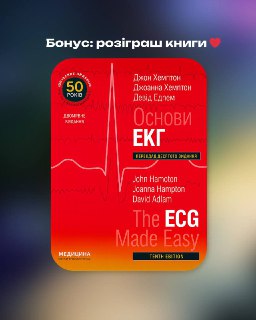

•Лекція за донат • ЕКГ: розбір випадкових плівок з практики + розіграш книги: Основи ЕКГ John Hamoton Дата: 30 грудн...